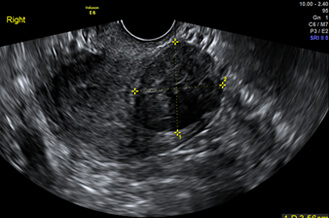

正常子宮

子宮肌瘤